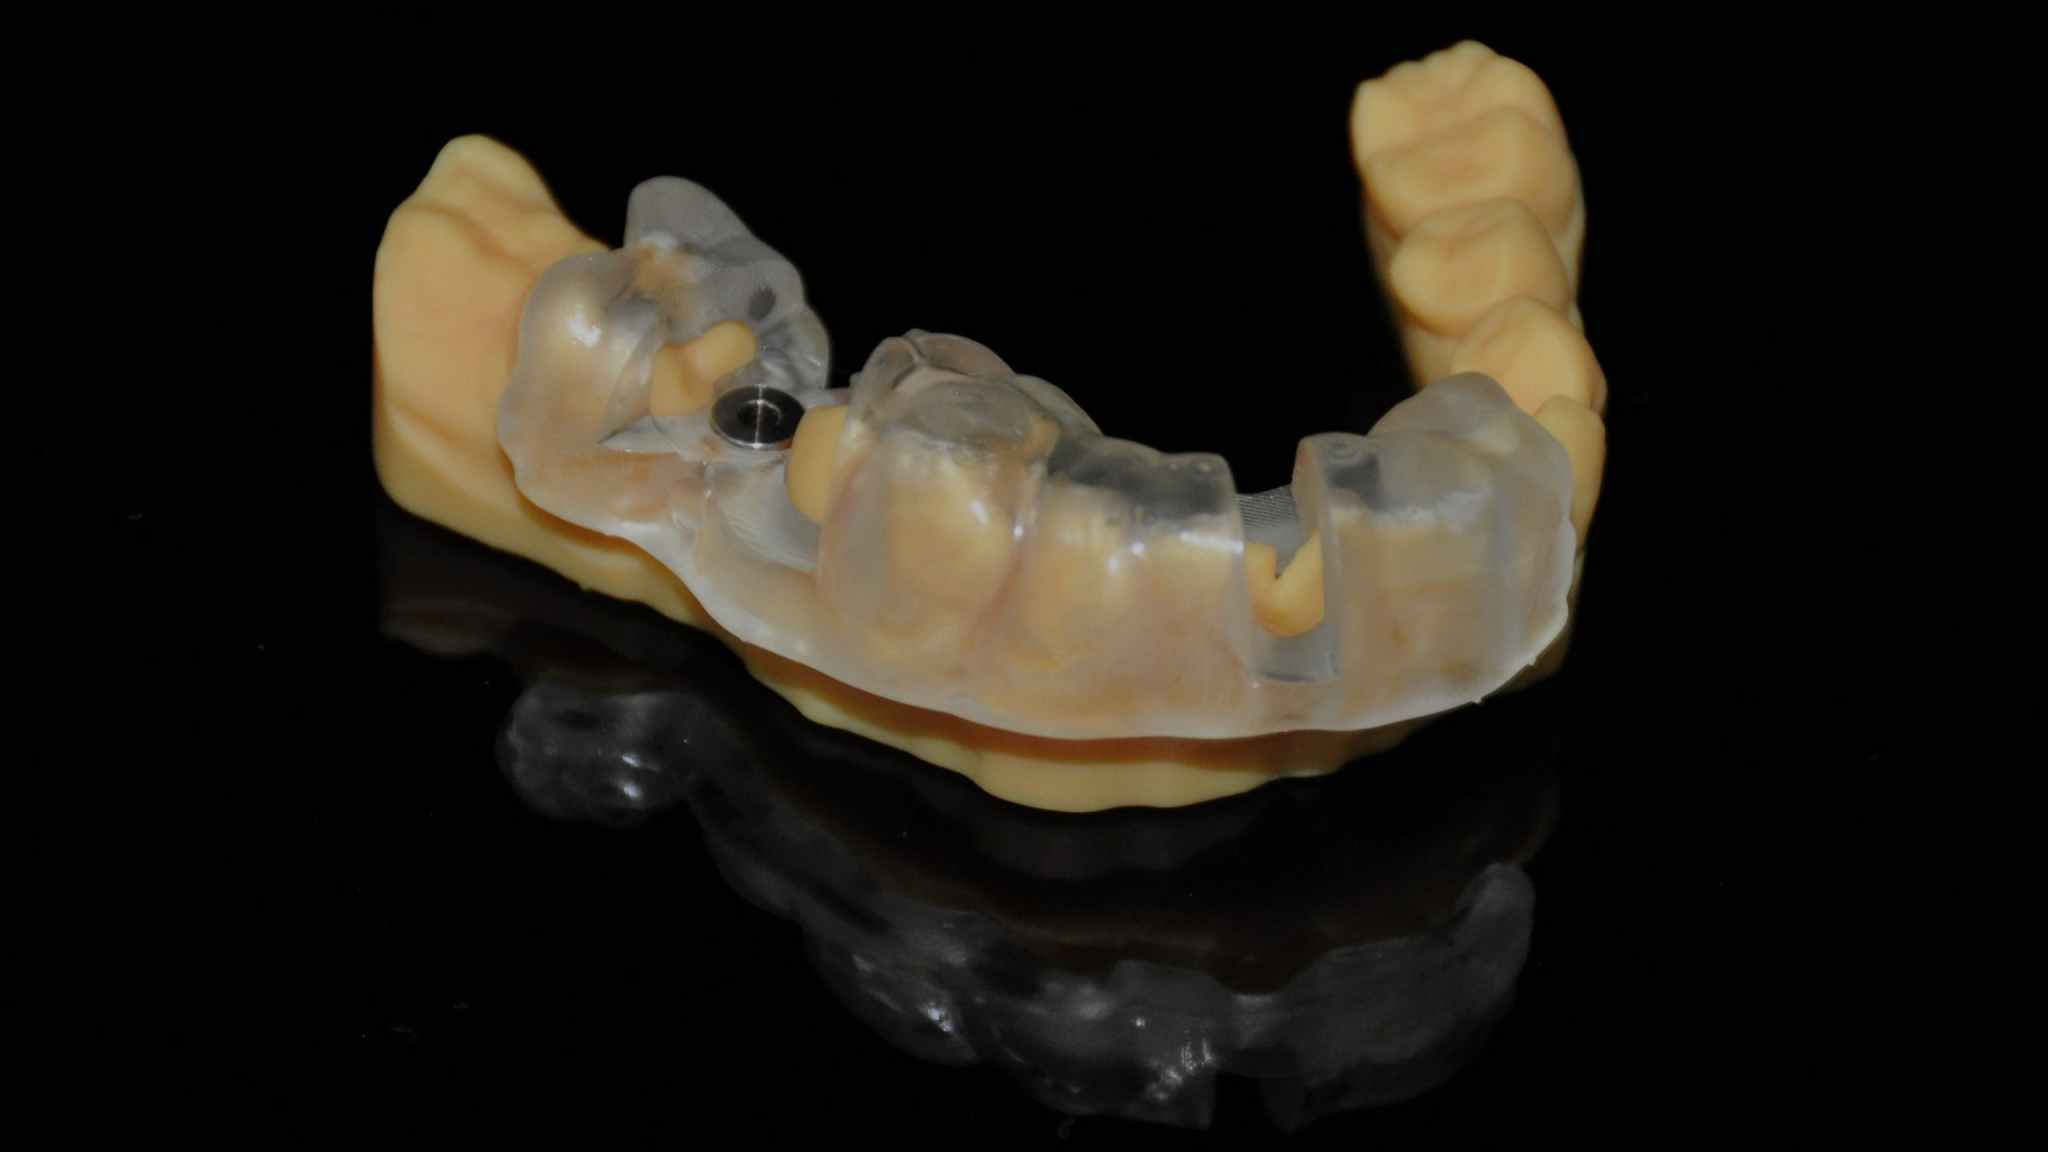

4. Print model & guide with AccuFab-D1

Printed model

Try-in on the printed model